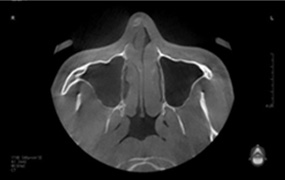

3D-CT

입체분석

을 통한

심층검사

수술 전 3D-CT 입체 분석을 통해

환자의 코 뼈는 물론 코 주변 연부 조직의

모양, 상태, 크기까지 정밀하게 검사하여

환자 개개인에 맞는 1:1 맞춤 수술을 계획합니다.

연골 비대칭 및

비중격 만곡증의 유무

하비갑개 비후 및

코막힘 문제해결

비중격 연골의

상태와 크기 분석

코 뼈의 넓이